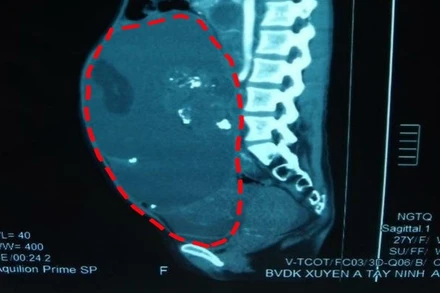

Hình ảnh khối u trước khi được bóc tách qua soi chụp. (Ảnh: Bệnh viện Xuyên Á)

Ngày 21-4, Bệnh viện đa khoa Xuyên Á, tỉnh Tây Ninh, cho biết vừa tiếp nhận người bệnh N.T.H. (27 tuổi, quê Tây Ninh) có khối u chiếm toàn bộ ổ bụng, gây ra các triệu chứng như đau nhói vùng bụng, cột sống thắt lưng, đồng thời do bướu quá to, chèn ép lồng ngực gây khó thở.